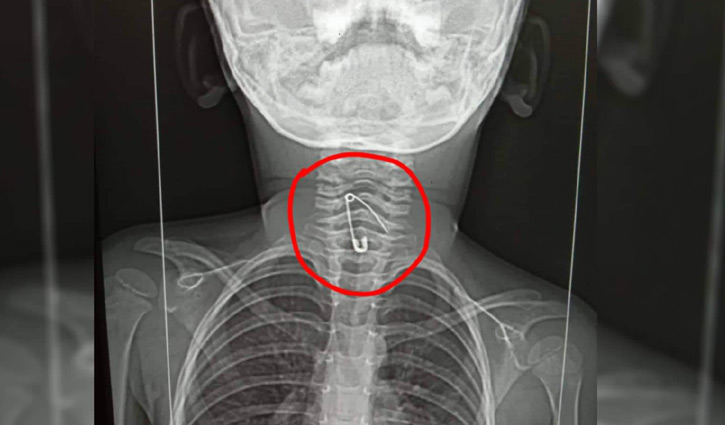

৫২ ঘণ্টা পর জিদনীর গলা থেকে সেপটিপিন অপসারণ

নাটোরের লালপুর উপজেলার শিশু সোহানা আক্তার জিদনীর (৩) গলায় আটকে যাওয়া সেপটিপিন অপসারণ করা হয়েছে। ঘটনার ৫২ ঘণ্টা পর শুক্রবার (২৬ আগস্ট) রাতে ঢাকা মেডিক্যাল কলেজ হাসপাতালের চিকিৎসকরা সেপটিপিনটি অপসারণ করতে সক্ষম হন।

হাসান আলী বলেন, খাদ্যনালীতে আটকে যাওয়া সেপটিপিন বের করার পর জিদনী এখন সুস্থ আছে।

খোঁজ নিয়ে জানা যায়, গত বুধবার সন্ধ্যায় মায়ের হাতে নুডুলস খাওয়ার সময় সেপটিপিন গিলে ফেলে শিশু জিদনী। এসময় সে অসুস্থ হয়ে পড়লে তাকে প্রথমে রাজশাহীর বাঘা উপজেলা স্বাস্থ্য কমপ্লেক্সে নিয়ে যাওয়া হয়। পরে তাকে রাজশাহী মেডিক্যাল কলেজ হাসপাতালে স্থানান্তর করা হয়। সেখানে সেফটিপিন বের করার পর্যাপ্ত ব্যবস্থা না থাকায় জিদনীকে ঢাকা মেডিক্যাল কলেজ হাসপাতালে নিয়ে যাওয়া হয়। পরে সেখানকার চিকিৎসকরা খাদ্যনালী থেকে সেপটিপিনটি অপসারণ করেন।